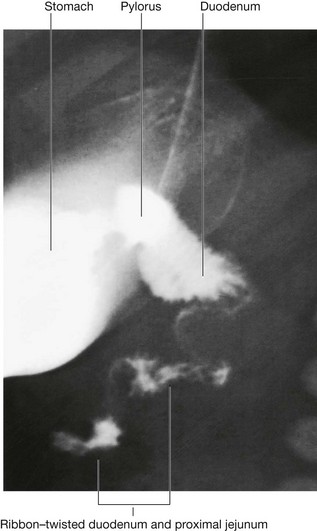

The transpyloric plane is a horizontal plane that transects the body through the lower aspect of vertebra LI (Fig. 4.16). It:

image is about midway between the jugular notch and the pubic symphysis, and crosses the costal margin on each side at roughly the ninth costal cartilage;

image crosses through the opening of the stomach into the duodenum (the pyloric orifice), which is just to the right of the body of LI; the duodenum then makes a characteristic C-shaped loop on the posterior abdominal wall and crosses the midline to open into the jejunum just to the left of the body of vertebra LII, whereas the head of the pancreas is enclosed by the loop of the duodenum, and the body of the pancreas extends across the midline to the left;

image crosses through the body of the pancreas; and

image approximates the position of the hila of the kidneys; though because the left kidney is slightly higher than the right, the transpyloric plane crosses through the inferior aspect of the left hilum and the superior part of the right hilum.

Fig. 4.16 Vertebral level LI.